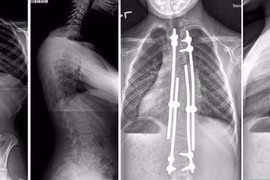

(khoahocdoisong.vn) - Biến dạng cột sống rất nặng và cứng nên bắt buộc phải phẫu thuật 2 đường. Phẫu thuật giúp chỉnh cong vẹo, trẻ cao thêm được 11-13cm. Hãy nhận biết các dấu hiệu trẻ bị biến dạng cột sống để cho trẻ đi khám sớm.